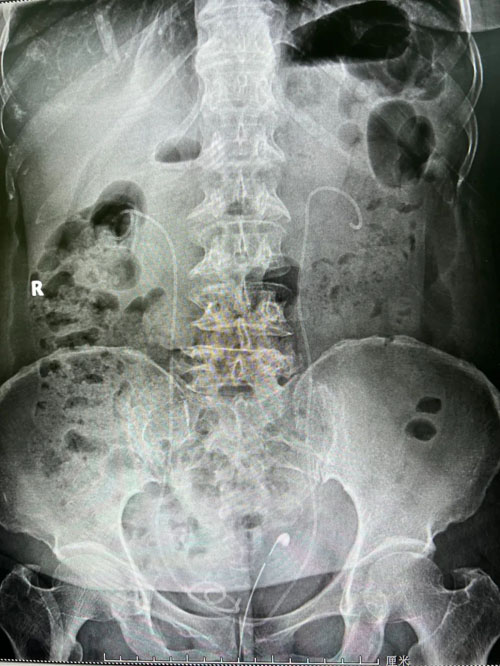

患者術(shù)前CT

副院長程廣舟和程波副主任認(rèn)真閱片、分析病情,認(rèn)為患者手術(shù)難點(diǎn)在于,患者雙側(cè)結(jié)石,且結(jié)石體積大、質(zhì)地硬,預(yù)計(jì)碎石清石會耗費(fèi)較長時(shí)間;患者既往結(jié)石手術(shù)史,解剖結(jié)構(gòu)復(fù)雜,腎臟積水不重,穿刺難度大;患者合并糖尿病,術(shù)前感染較重,手術(shù)過程中,腎盂壓力增大,細(xì)菌進(jìn)入血液引起菌血癥甚至膿毒血癥的風(fēng)險(xiǎn)高,時(shí)間越長,風(fēng)險(xiǎn)越大。雖然手術(shù)難度大,但考慮患者的經(jīng)濟(jì)條件,經(jīng)過全科討論,決定行一期雙側(cè)手術(shù),術(shù)中根據(jù)情況變更手術(shù)方案。

在程廣舟副院長的指導(dǎo)下,程波副主任為患者實(shí)施手術(shù)。患者結(jié)石質(zhì)地堅(jiān)硬,碎石困難,在麻醉醫(yī)師與手術(shù)室護(hù)士的通力配合下,該患者順利完成雙側(cè)“無管化”經(jīng)皮腎鏡碎石取石術(shù)。從精準(zhǔn)穿刺到擴(kuò)張,再到手術(shù)結(jié)束,僅僅用了1個(gè)半小時(shí)。手術(shù)過程中,麻醉醫(yī)生密切觀察患者情況,術(shù)后患者順利復(fù)蘇,術(shù)后恢復(fù)良好,未出現(xiàn)發(fā)熱情況,術(shù)后復(fù)查腹部平片未見結(jié)石殘留,患者及家屬非常滿意。